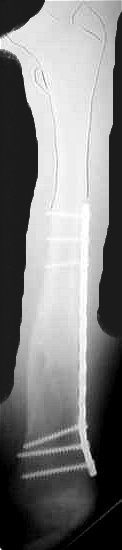

From: Kanlic, Enes M. M.D.

In deciding how to treat pediatric femur fractures the type of fracture and

weight of the patient are more important to be considered than the age.

"Problem" fractures (comminuted, long spiral, high sub or pertrochanteric,

supracondylar fx) do represent 43% of cases in Flynn, 2001 study, and 55% in

Heinrich,1994 study. For those fractures PERCUTANEOUS SUBMUSCULAR AND

EPIPERIOSTEAL BRIDGE PLATING is the best method.

Group of us (D. Smith, J. Anglen, S. Morgan, R. Pesantez, P.Cole) have done

more than 40 cases. Average OR time 103 minutes, x-ray time 105 seconds. No

infections or nonunions. All had excellent clinical result. Complications:

one temporary peroneal palsy, one valgus malalignment and one plate bending

after new injury (reduced closed and healed uneventfully).

Bridge plating provides elastic fixation for all type of fractures without

the need for bracing and casting, with excellent and reproducible results.

Plates are removed 6-12 month after injury.

In my opinion, stable fractures (transverse and short oblique shaft

fractures) should be treated with elastic intramedullary nails, what is even

less invasive than bridge plating.

Problems with other methods are:

1. Intramedullary elastic nailing: can not sufficiently stabilized "problem

fractures" (see above), in Flynn's study 70% of patients had to be put in

I am attaching one of my cases.

Enes M. Kanlic, MD, PhD